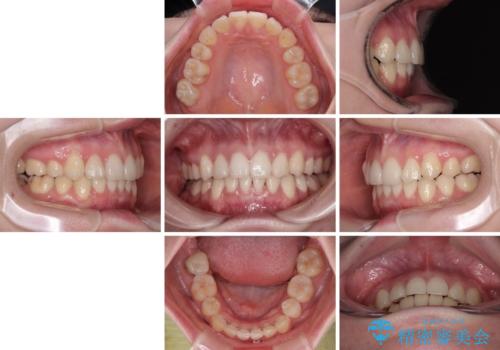

上下の八重歯とクロスバイト ワイヤー装置での抜歯矯正

- 八重歯とクロスバイトを気にして来院された患者様です。

上下ともに八重歯が顕著であり、前歯のクロスバイトがあったため、上下左右の第一小臼歯4本を抜歯し、ワイヤー装置での抜歯矯正を行うこととしました。

20歳ということもあり、歯の移動速度が非常に速く、1年強という短期間であっという間に治療を終えることができました。